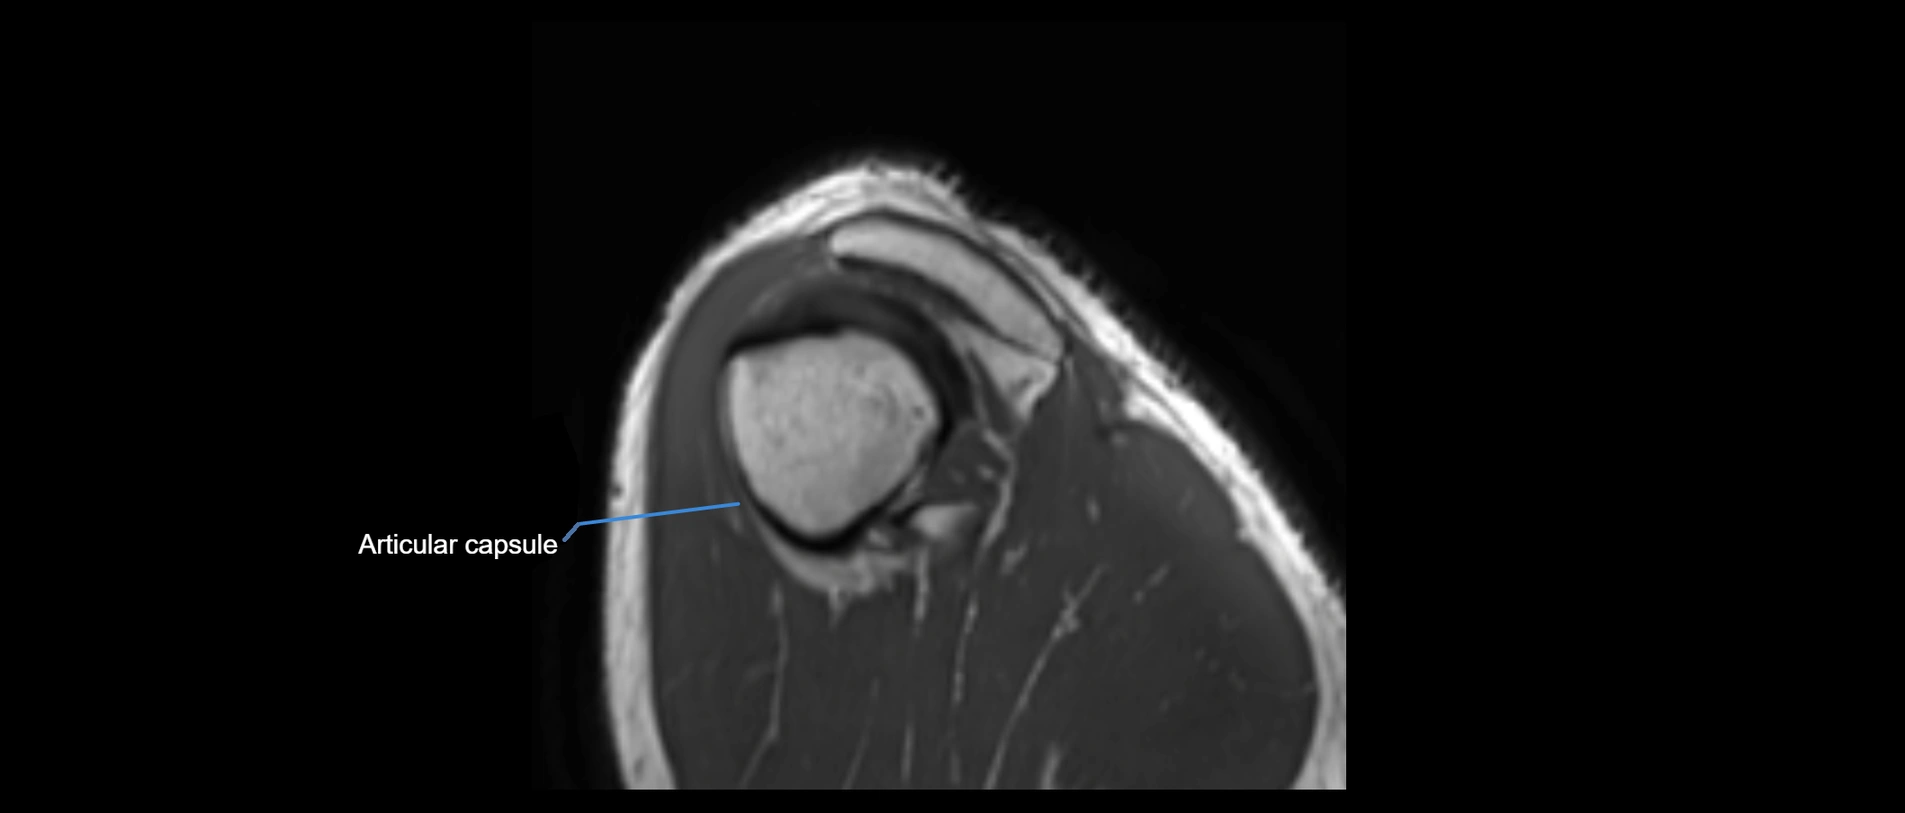

CT image

image